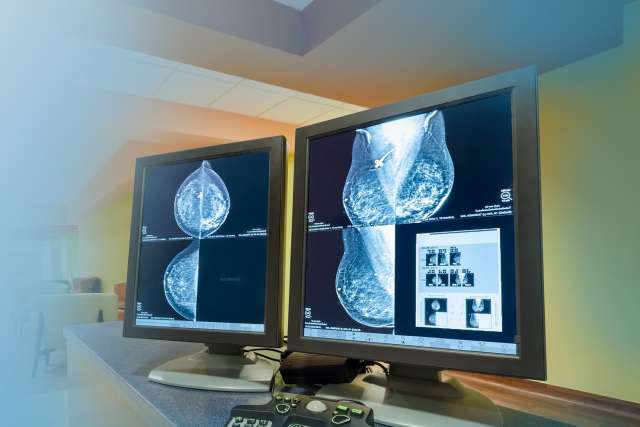

3D mammograms (breast tomosynthesis): Mammograms are low-dose breast X-rays. A technician takes X-rays from several views and a computer compiles those images into a 3D picture that allows us to see breast tissue clearly.

Screening mammogram: We perform screening mammograms for patients who have no signs of breast cancer. These tests involve two views of the breast. Screening mammograms are one of the best tools we have for finding cancer in early stages.

Diagnostic mammogram: If a patient has symptoms that could point to breast cancer, we do a diagnostic mammogram. It involves several views of the breast and focuses on particular areas of concern. We can use these tests to diagnose the cause of breast changes, such as an unusual lump, pain or nipple discharge.

Breast ultrasound: Ultrasound uses high-frequency sound waves to generate breast tissue images. We may use ultrasound in addition to a mammogram to get a closer look at breast changes. For example, an ultrasound can help us differentiate between a fluid-filled cyst, which is highly unlikely to be cancer, and a solid mass, which may need further testing. Ultrasounds are also often useful for women with dense breast tissue, for whom mammograms may not be as reliable.

Breast MRI: We often use MRIs for women who have been diagnosed with breast cancer. These tests can help measure the size of a mass, look for other tumors or check for tumors in the opposite breast. MRIs use magnets and radio waves to produce images of the breasts in all directions: top to bottom, left to right and front to back. Some women with a high risk for breast cancer may benefit from screening MRIs along with yearly mammograms.